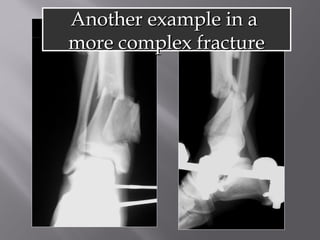

AAnnootthheerr eexxaammppllee iinn aa

mmoorree ccoommpplleexx ffrraaccttuurree

5 months